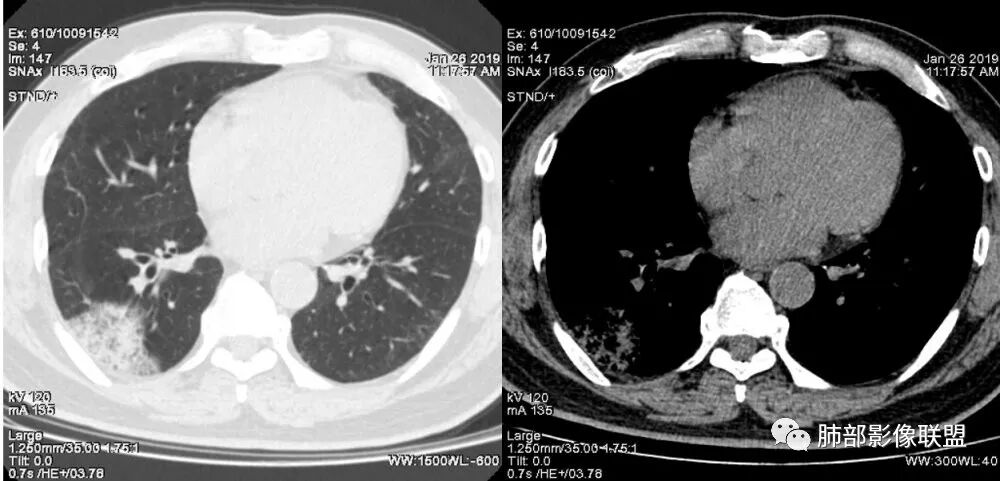

老年女性,右肺下叶沿胸膜下大片状高密度影,外周磨玻璃影,边界较清,内可见蜂窝征及支气管充气征,考虑肺炎型肺癌。

老年女性,咳嗽咳痰病史,右肺下叶大片磨玻璃实变影,胸膜下分布,支气管进入后扩张、僵直,磨玻璃影边界清楚,考虑粘液腺癌。鉴别肺炎。

右肺下叶基底段靠胸膜实变/磨玻璃混杂密度影,边界清楚,内见多发空泡(蜂窝样趋势改变?); 临床:咳嗽咳痰,无发热、胸痛; 考虑腺癌:无发热,感染性病变不首先考虑;部分层面形态类楔形,鉴别肺栓塞

老年女性,右下肺实变影,病灶里有小叶内间质增厚,周围GGo,支气管扩张,粘液性腺癌?淋巴瘤?

中年女性,咳嗽咳痰。右肺下叶片状高密度影,部分实性密度,周围见边界清晰磨玻璃影,内见小空泡,实性区部分支气管堵塞,有重力效应,考虑肺炎型肺癌,建议查痰脱落细胞。

老年人,右肺下叶斑片状阴影,病灶有膨胀性,边缘可见磨玻璃影,其边界清晰,内见僵硬的支气管,部分支气管扩张,首先考虑占位性病变,粘液性腺癌可能。鉴别感染性病变,后者边缘多有收缩性改变或者平直,内部支气管走形自然。

1.本例病灶较大片混杂密度影,胸膜下分布为主(未沿着支气管分布),该分布特点可见于大叶性肺炎、干酪性肺炎、淋巴瘤及粘液腺癌等。可惜未提供增强扫描图像。

2.病灶示中央实变区,周围GGO,可见明显小叶间隔增厚,GGO边界清楚,应当考虑到恶性病变的可能性。肺炎因炎性水肿及渗出,影像上边界常模糊不清,注意早期粘液腺癌可出现似清非清的边界。粘液腺癌因粘液成份较多,密度一般偏低,纵隔窗病灶常会消隐或范围会明显缩小,这不同于炎性实变。

3.病灶内支气管走形略显僵直,侧支少(粘液阻塞),也符合肺腺癌的枯树枝征。而大叶性肺炎的支气管是管壁光整、通畅、自然,结核的支气管常常壁增厚,甚至狭窄后扩张;